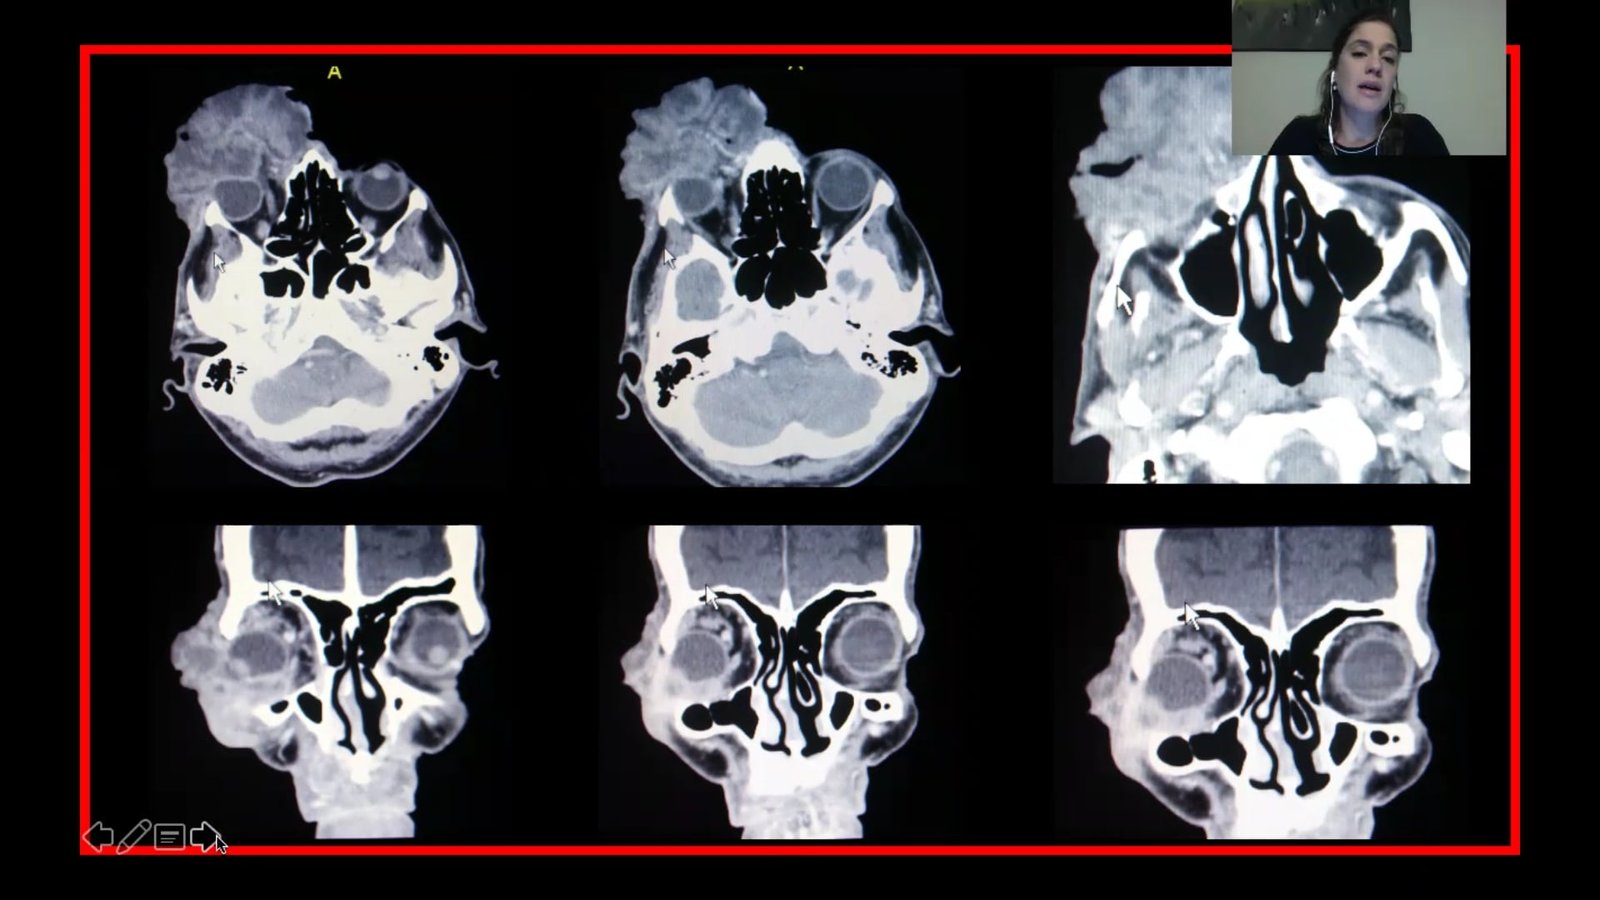

Módulo 1: Tumores Orbitarios

David Pelayes, Daniel Weil, Alejandra Billagra, Lorena Di Nisio, José Luis Tovilla, Solón Serpa